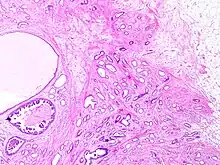

Histopathology of tubular carcinoma, low magnification, H&E stain. It shows the typical features of invasive breast cancer with infiltrative growth pattern, here including invasion into adipose tissue and with an associated fibrous or desmoplastic stromal response. It has the criterion of more than 90% of the tumor composed of small, ovoid or angulated tubules with open lumina. Ductal carcinoma in situ is seen at left as lumina with micropapillary formations (under the larger bland cyst), and was presumably the precursor lesion for the ductal carcinoma.[1]

Tubular carcinomas are generally around 1 cm. or smaller, and are made up of tubules. They are usually low-grade.[2] Elastosis has been noted as common but is not present in all cases.[11]